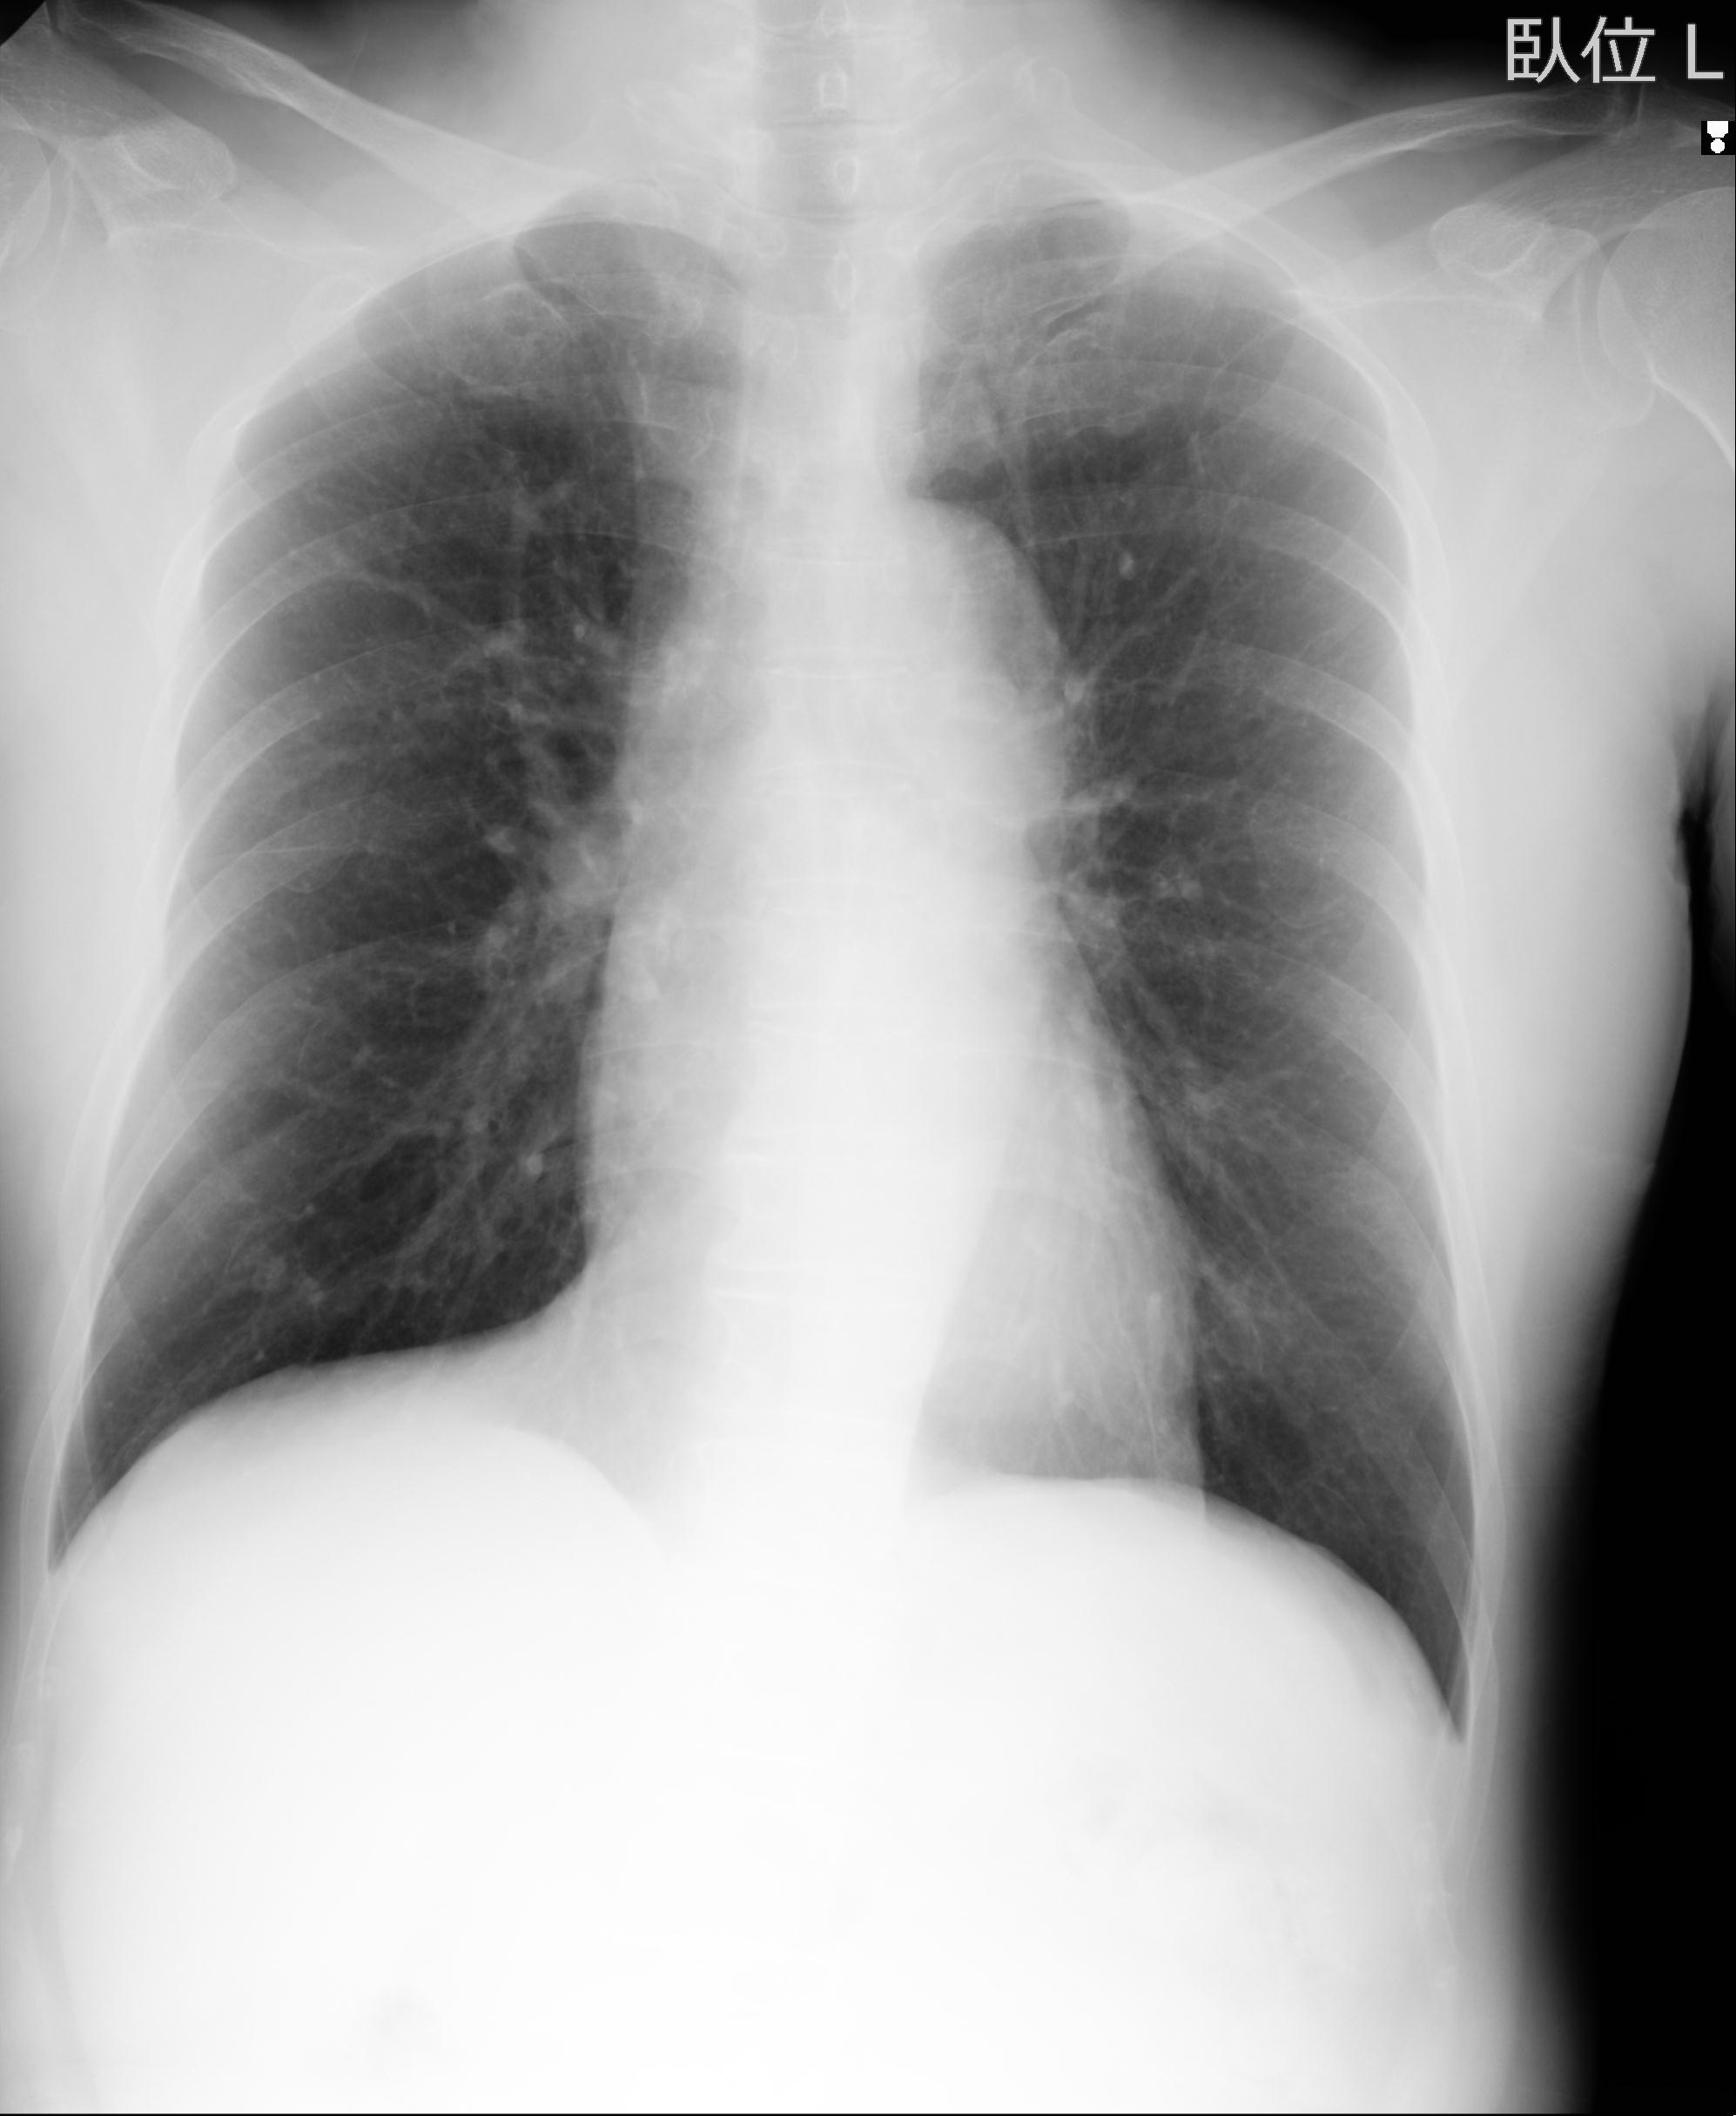

60058 3/9 11/4 右肩 2R+MRI 73歳男性 肩腱板損傷